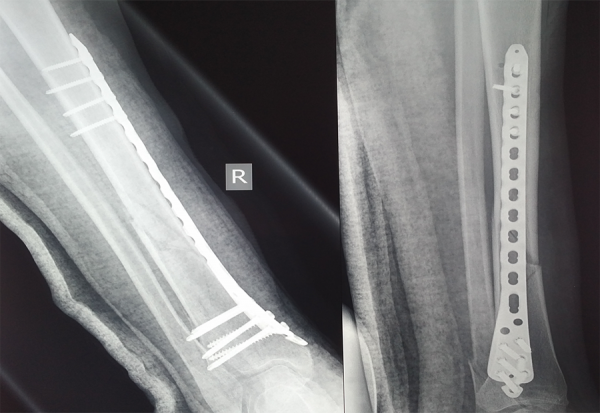

Η χειρουργική τραύματος αποτελεί έναν εξειδικευμένο τομέα της ορθοπεδικής που ασχολείται με την αποκατάσταση των οστικών και μαλακών ιστικών τραυματισμών που προκαλούνται από ατυχήματα, πτώσεις ή άλλες κακώσεις. Στόχος της είναι η άμεση...